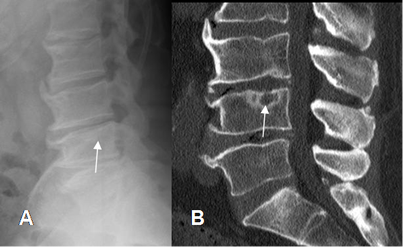

La afectación de la columna cervical y lumbar, produce osteofitos, disminución en la amplitud de los espacios e hipertrofia de articulaciones intervertebrales, con canal estrecho asociado. (Fig 12, 13, 14 y 15).

Fig 12. Artropatía degenerativa en columna.

A: Rx lateral y B: RM gradiente eco (GE) sagital, de la columna cervical. Presencia de osteofitos anteriores y posteriores, muy bien definidos en el GE, que es la secuencia de elección para su detección.

Fig 13. Artropatía degenerativa.

A y B: TAC cervical axial. Osteofitos anteriores e hipertrofia de articulación intervertebral derecha, que disminuye la amplitud del agujero de conjunción. (Flecha negra).